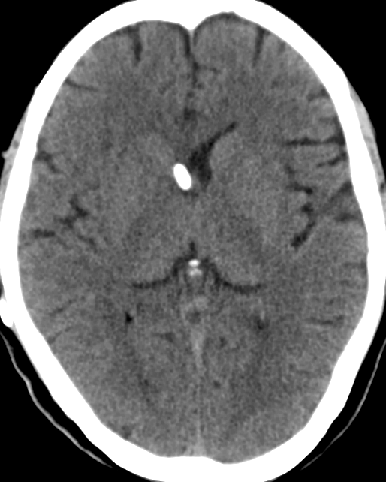

2013-8-2 CT

腰穿脑压240